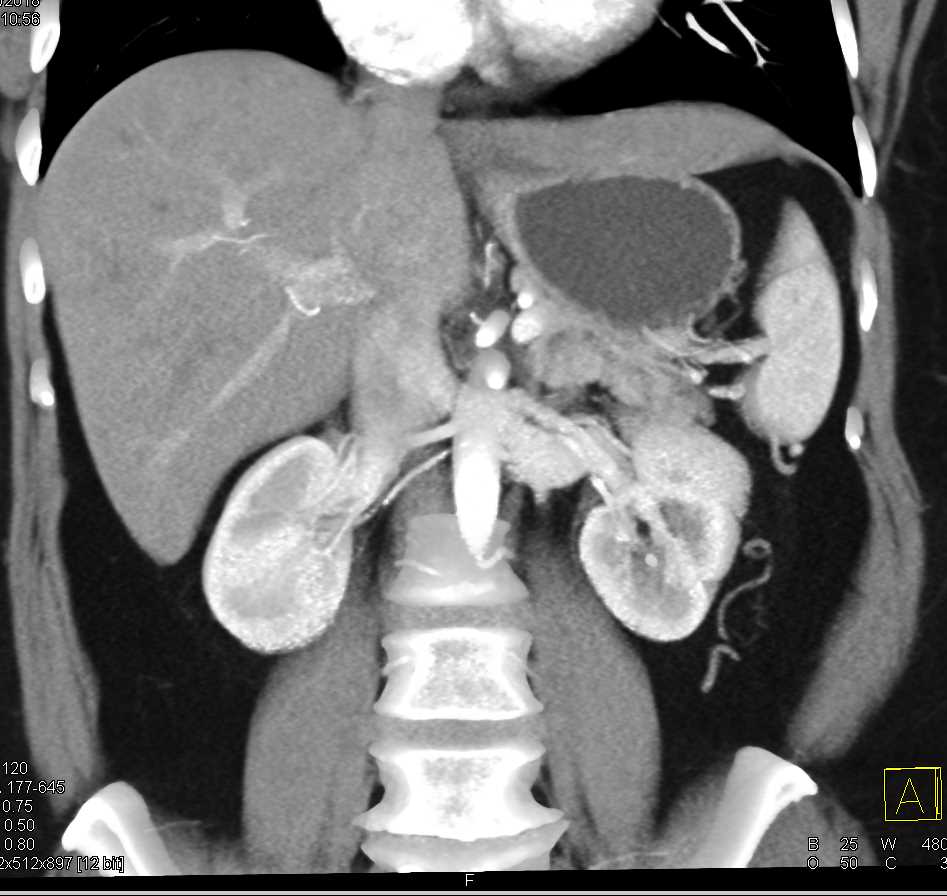

Neuroendocrine Tumor Body of Pancreas